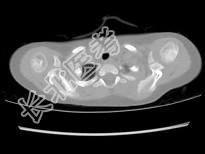

单项选择题女,2岁半, 无痛性右肩部肿块,结合图像, 最可能的诊断是 ( )

A、朗格汉斯细胞增多症

B、尤文肉瘤

C、骨髓瘤

D、霍奇金病

E、淋巴瘤